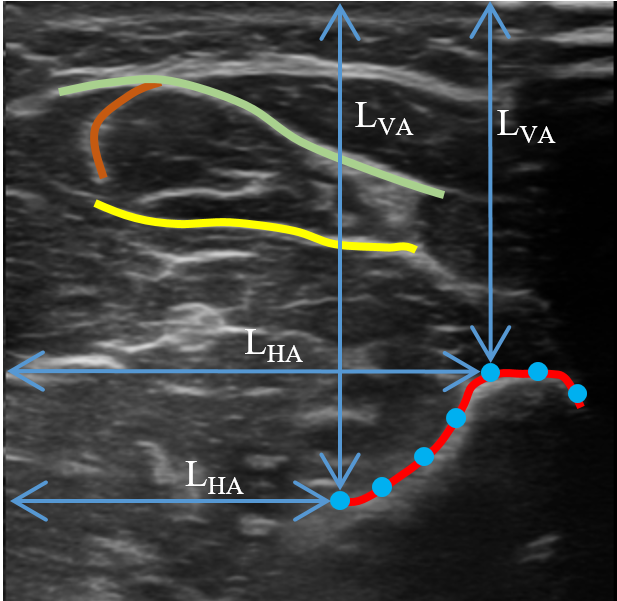

Refer to caption

Fig. 9: Illustration of tissue interface annotations on B-mode images. The four curves with clear ending points on both sides are carefully annotated. The blue dots are the sampling points generated on one selected interface.

4.5.1 Target Localization Accuracy

US images often exhibit distinct curves caused by the boundaries between various tissues. Such interfaces located at different parts of the image can be used as good biomarkers to calculate the TLA between the uncompressed images and deformed/corrected images. A representative illustration is depicted in Fig. 9, where we carefully annotated the selected four distinct interfaces. Each selected interface should have clear ending points at both sides to ensure its completeness on a set of corresponding uncompressed, deformed, and corrected images. To compute TLA, we first evenly (every 555 pixels in the horizontal axis) sampled the measurement points from all interfaces. Then horizontal and vertical distances (LHAsubscript𝐿𝐻𝐴L_{HA} and LVAsubscript𝐿𝑉𝐴L_{VA}) at each sampling point were computed (see Fig. 9). Then TLA at each sampling point can be calculated as HA=LHAiLHAgtLHAgt𝐻𝐴normsubscriptsuperscript𝐿𝑖𝐻𝐴subscriptsuperscript𝐿𝑔𝑡𝐻𝐴subscriptsuperscript𝐿𝑔𝑡𝐻𝐴HA=\frac{\|L^{i}_{HA}-L^{gt}_{HA}\|}{L^{gt}_{HA}} and VA=LVAiLVAgtLVAgt𝑉𝐴normsubscriptsuperscript𝐿𝑖𝑉𝐴subscriptsuperscript𝐿𝑔𝑡𝑉𝐴subscriptsuperscript𝐿𝑔𝑡𝑉𝐴VA=\frac{\|L^{i}_{VA}-L^{gt}_{VA}\|}{L^{gt}_{VA}}, where i𝑖i is the deformed or corrected images. The average TLA (HA and VA) computed on unseen scans from six volunteers are summarized in TABLE 3.